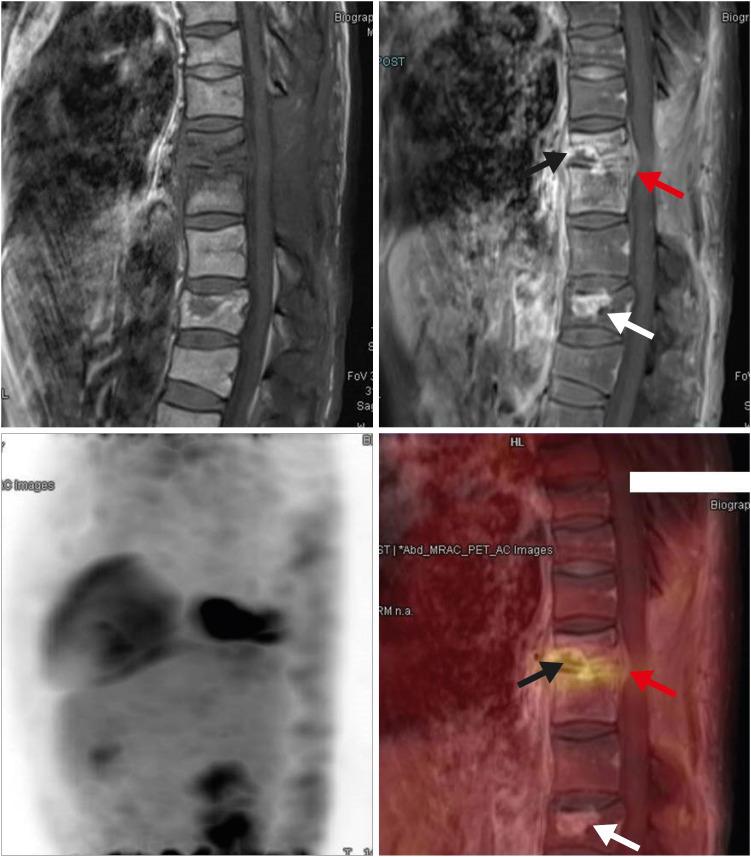

Magnetic resonance imaging (MRI) is the preferred imaging method for evaluating treatment response in spine infection. However, there are still no definite correlation between follow-up MRI findings and clinical status. Recently, Fluorine-18 fluorodeoxyglucose positron emission tomography (18F-FDG PET) shows great potential as diagnostic and monitoring options. Simultaneous 18F-FDG PET/MRI makes us to expect a huge synergic effect on diagnosis and evaluation of treatment response with metabolic and anatomical advantages in spine infection. We introduce an application of 18F-FDG PET/MRI for evaluating residual lesion in the patient with pyogenic spine infection.

磁共振成像(MRI)是评估脊柱感染治疗反应的首选成像方法。然而,随访MRI表现与临床状况之间仍无明确的相关性。最近,氟-18氟脱氧葡萄糖正电子发射断层扫描(18F-FDG PET)作为诊断和监测手段显示出巨大潜力。同时进行的18F-FDG PET/MRI使我们期望在脊柱感染的诊断和治疗反应评估方面产生巨大的协同效应,兼具代谢和解剖学优势。我们介绍了18F-FDG PET/MRI在评估化脓性脊柱感染患者残余病变中的应用。